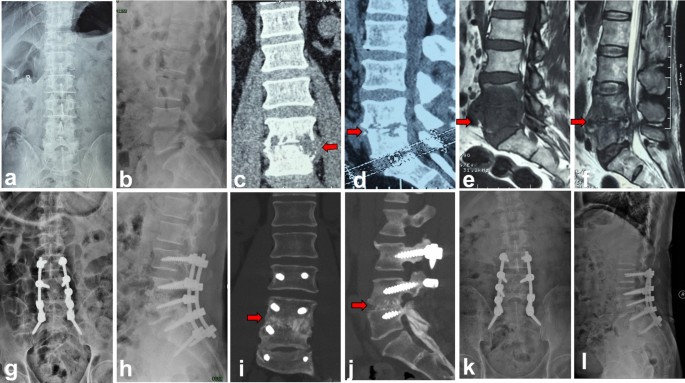

The comparison of the fusion rate, average fusion time, lumbar lordosis and sagittal angle results between group A and group B were summarized in Table 2 and representative radiological images of one patient in each group were shown in Figs. 3 and 4. The mean preoperative lumbar lordosis angles of group A and group B were 45.7° ± 8.9° and 44.1° ± 10.0°. These were corrected to 51.2° ± 7.2° (P < 0.05) and 52.6° ± 7.7° (P < 0.05) at the last follow-up, respectively. The mean preoperative sagittal Cobb angle of group A was 5.9° ± 3.3°. This was corrected to 14.1° ± 4.9° (P < 0.05) after the immediate operation. There was a mean loss of 4.6° in the follow-up period and the mean sagittal Cobb angle was 9.5° ± 3.2° at the last follow-up. In Group B, the mean preoperative sagittal Cobb angle was 6.1° ± 4.9°. This was improved to 15.5° ± 5.0° after immediate surgery and 11.5° ± 5.0° at the final follow-up (with a mean loss angle of 3.75°), indicating a significant correction. Compared with the preoperative values, the mean sagittal Cobb angles of group A and group B were significantly improved at the last follow-up.

Autologous spinous process group (group B). A 62-year-old male with L4–5 lumbar pyogenic spondylitis. (a–f) Preoperative MRI and CT showed there were bone destruction, intervertebral space stenosis and massive paravertebral abscess (red arrow) at L4–5. (g,h) Postoperative X-ray showed autologous spinous process, screws and rods were in good location. (i–l) CT taken at 5 months after operation showed solid bone fusion between L4 and L5.